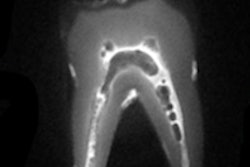

Building on the technology of the 2D panoramic images provided by the CS 8100, the CS 8100 3D offers 3D imaging and 3D model scanning in one unit. The system captures images with 1:1 accuracy without distortion or overlap of anatomy. Selectable 3D programs give endodontists control of the image size, resolution, and dose, providing an EndoHD mode (5 x 5 cm), for high-resolution scans with 75 µm precision to capture the details of root and canal morphology.

Endodontists can change image contrast according to their diagnostic needs with the RVG 6200's endodontic filter, which optimizes contrast values throughout the entire range of the image. The system's sharpness filter enables clinicians to customize the appearance of images to their preferred look and feel. The filter displays contrast changes in real-time, and six different sharpness options on the dynamic slider bar help practitioners find their ideal image cosmetic, including a high-sharpening filter for endodontic procedures, according to Carestream.